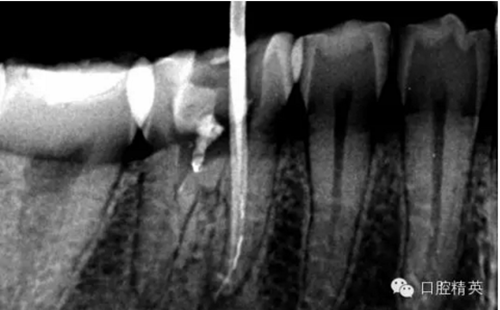

患者,肖某,男,32歲,#36慢性牙髓炎。遠(yuǎn)中舌根根尖1/3彎曲而且鈣化不通,我用盡辦法疏通了很久也沒到達(dá)WL,(我一直在幻想,要是有超聲系統(tǒng)該多好,可是現(xiàn)實很骨感,我們單位暫時還沒有超聲系統(tǒng)),后來我放棄了,最后的根充片顯示遠(yuǎn)中舌根充填物距根尖端2.84mm,屬于欠填范圍(根管內(nèi)充填物距根尖端2mm以上),其它三根根尖1/3鈣化相對沒那么嚴(yán)重,根充片顯示屬于恰填范圍(根管內(nèi)充填物距根尖端0.5~2mm)。歡迎網(wǎng)友們針對這個病例提出寶貴的建議!

9.png

10.png